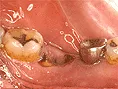

| 自費ブリッジ |

通常のブリッジは 強度を維持するため大きくなります メタルボンドは 適正なサイズで色も自然です ■長所 ・金属が見えない ■短所 ・前後の歯を削り犠牲にする ・高い |